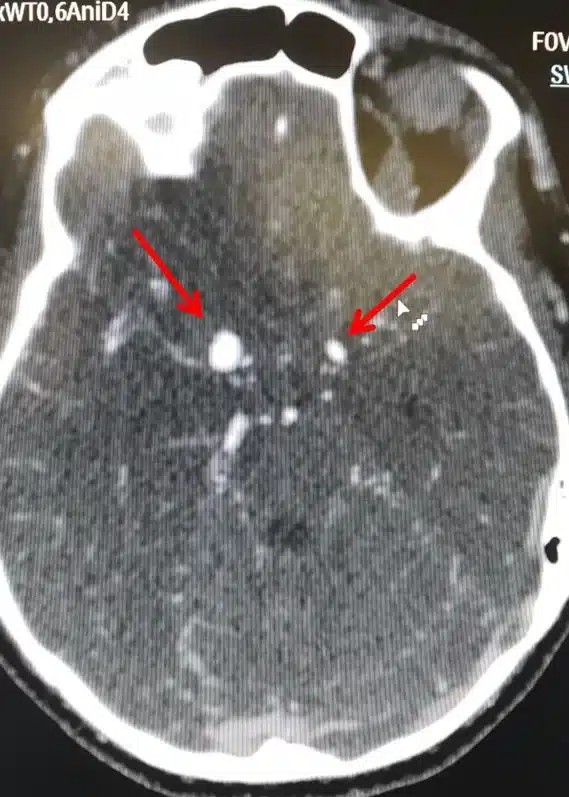

Υπάρχουν δύο μορφές εγκεφαλικών ανευρυσμάτων, το σακοειδές και το ατρακτοειδές ανεύρυσμα.

Η συχνότερη μορφή που μπορεί να πάρει ένα ανεύρυσμα είναι η ασκοειδής ή σακοειδής, δηλαδή σχηματίζεται στο αδύνατο σημείο της αρτηρίας ένας σάκος με μίσχο που τον ενώνει με την υπόλοιπη αρτηρία. Φαίνεται σαν ένα μούρο που προβάλλει από μια αρτηρία. Συνήθως αναπτύσσεται σε περιοχές διχασμού αγγείων.

Εκτιμάται ότι 3,5% έως 6% του γενικού πληθυσμού έχουν σακοειδές ανεύρυσμα. Στο 15% έως 30% των περιπτώσεων αυτών, υπάρχουν περισσότερα από ένα σακοειδή ανευρύσματα.